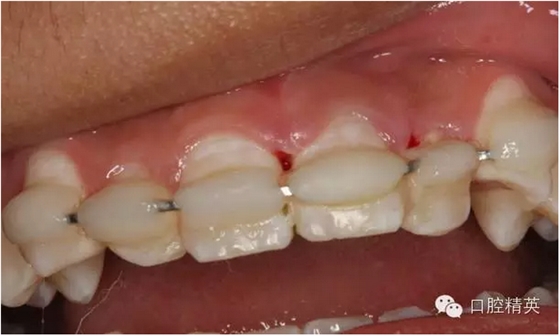

圖1.一周后復(fù)診拆線、唇側(cè)齦乳頭水腫。

圖3.拆線后唇側(cè)觀,牙齦乳頭輕度水腫

圖4.腭側(cè)觀21齦乳頭水腫明顯

圖6.固定一個(gè)月后的唇側(cè)影像,牙齦及粘膜正常?;颊邿o(wú)任何自覺(jué)癥狀。

圖7.腭側(cè)口內(nèi)像,齦乳頭水腫消失

圖13.拋光完畢的牙面,齦乳頭色澤正常,無(wú)牙周袋。21不松動(dòng)